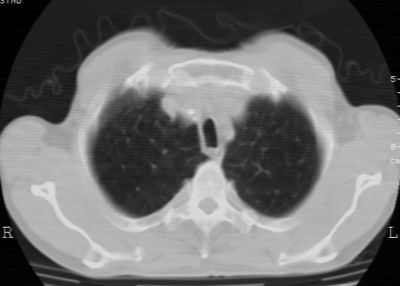

标题: CT24783:m71,既往肺心病史3年,现咳嗽,憋喘。 [打印本页]

标题: CT24783:m71,既往肺心病史3年,现咳嗽,憋喘。

1、左肺上叶spn,毛刺+分叶+血管集束征,考虑周围型肺癌可能性大

2、全小叶性肺气肿。

1)左肺上叶周围型肺癌可能。2)两肺全小叶型肺气肿。

左上周围型肺癌,全小叶型肺气肿。